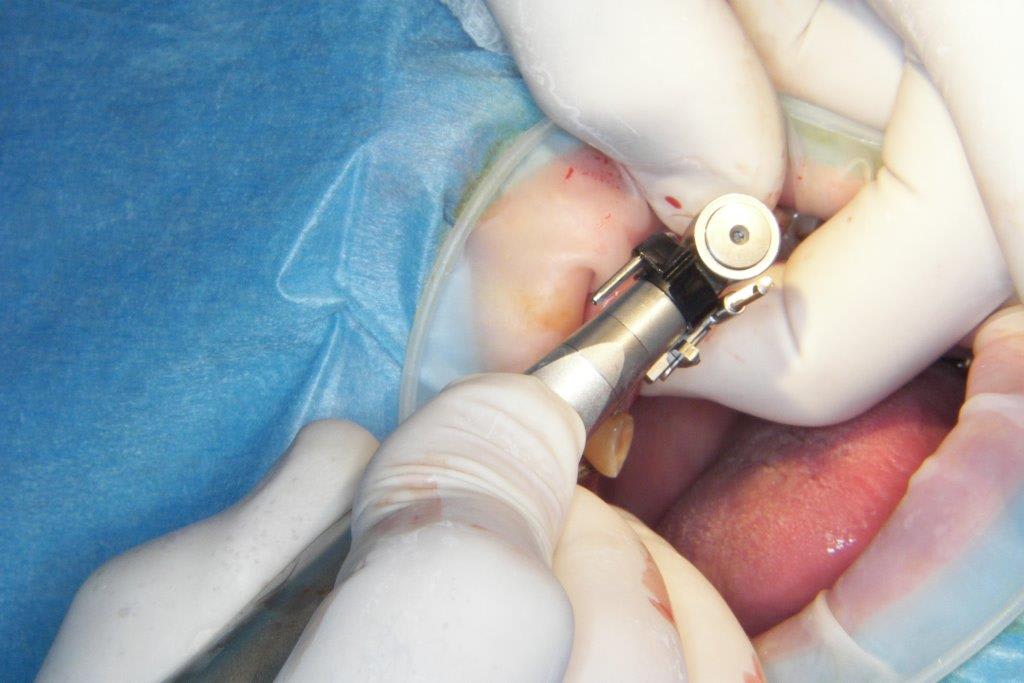

pour ceux que ça intéressent, une petite utilisation d'expansion de la paroi palatine, sur une avulsion d’incisive(racine fendue). toutes mes excuses pour la mauvaise qualité des photos.